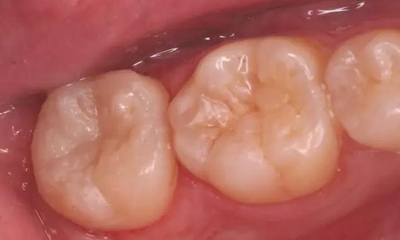

圖10 移除“印章”,合面窩溝形態(tài)得到較好復(fù)制

光固化,完成充填,調(diào)合、拋光

圖11 術(shù)后X線片:37恰填,遠(yuǎn)中鄰面樹脂充填物密合,無懸突。